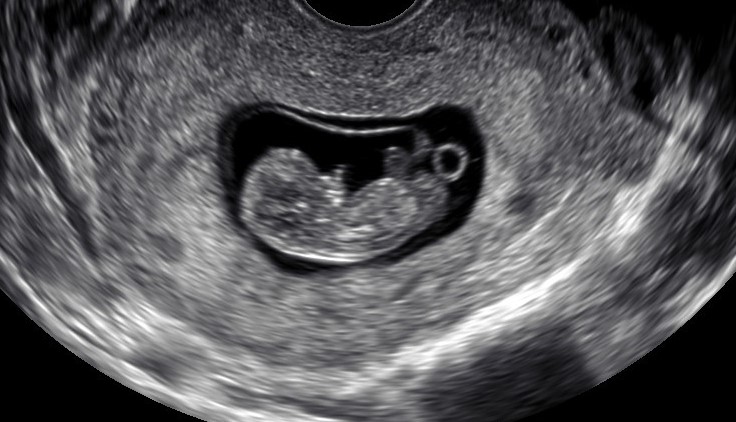

With beaming smiles and giddy excitement, Mike Black and Travis Wood show off an ultrasound photo of their nine-week-old, unborn baby.

Getting the photo required a 4,000-kilometre trip from Slave Lake, Alta., to Ottawa, where the couple’s surrogate lives and was getting an ultrasound. It’s an experience Black describes as “life-changing.”

An ultrasound photo of a nine-week-old fetus in its surrogate’s womb. The baby’s intended parents travelled from Alberta to Ontario to attend the ultrasound with their surrogate. Travis Wood/Handout